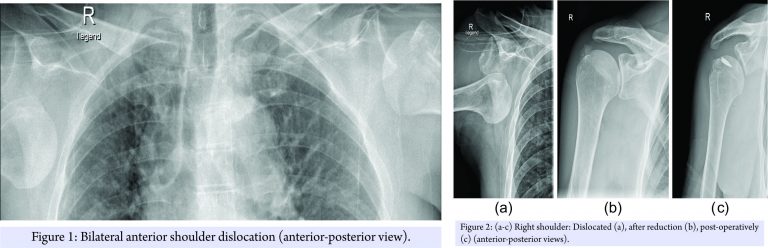

The patient was managed acutely on the slope and in our emergency room, according to ATLS principles, with a presenting GCS of 10 – E3V3M4. Full clinical examination was supplemented with imaging including a FAST scan and radiographs of shoulder joints, thorax, and pelvis. These confirmed the clinically suspected bilateral anterior shoulder dislocation combined with a four-part proximal humerus fracture on the left side and an osseous rotator cuff avulsion on the right side. The patient was neurovascular intact (Fig. 1, 2a and 3a).

In the emergency room, both dislocations were consecutively reduced under sedation using the traction-counteraction-technique (Fig. 2b and 3b). No neurovascular deficit was detected post reduction. The right shoulder was immobilized in a Gilchrist bandage and the left shoulder in a Desault’s bandage before performing a computed tomography (CT)-scan of the head to successfully eliminate possible cerebral hemorrhage or skull vault injuries.

As the patients recovering progressed, a magnetic resonance imaging (MRI) scan of the right shoulder was performed 3-day post-injury to clarify the soft-tissue damage and subsequently a single-row rotator cuff repair using two 5.5 mm TwinFix® anchors (Smith & Nephew; London, United Kingdom) was performed. An additional Pulley-lesion was treated with a biceps tenodesis with fixation of the tendon to the intertubercular sulcus using a 5.5 mm Footprint® anchor (Smith & Nephew; London, United Kingdom). The Hill–Sachs lesion was insignificant and did not require any further treatment (Fig. 2c). Post-operatively, the left shoulder was immobilized in a Velpeau-sling for 4 weeks and the right shoulder in an abduction splint for 6 weeks. Passive mobilization of both shoulders was started immediately on the first post-operative day, followed by increasing active and assistive mobilization. On the right shoulder, progressive adduction and a steady build-up of strength were initiated after 6 weeks. On the left shoulder, full mobilization was allowed following clinical and radiological confirmation of fracture consolidation. Physiotherapy (3 times a week), aquatic therapy (2 times a week), and a 3-week stay in a rehabilitation facility 2-month post-injury completed the post-operative care. The patient was discharged in good general condition with a total inpatient stay of 11 days. The 30-day follow-up assessment showed a still restricted range of movement while the 6-month follow-up assessment demonstrated bilateral considerably improved range of movement (Table 1). At the 2-year follow-up assessment still no evidence of implant failure, recurrence of dislocation or instability was observed.